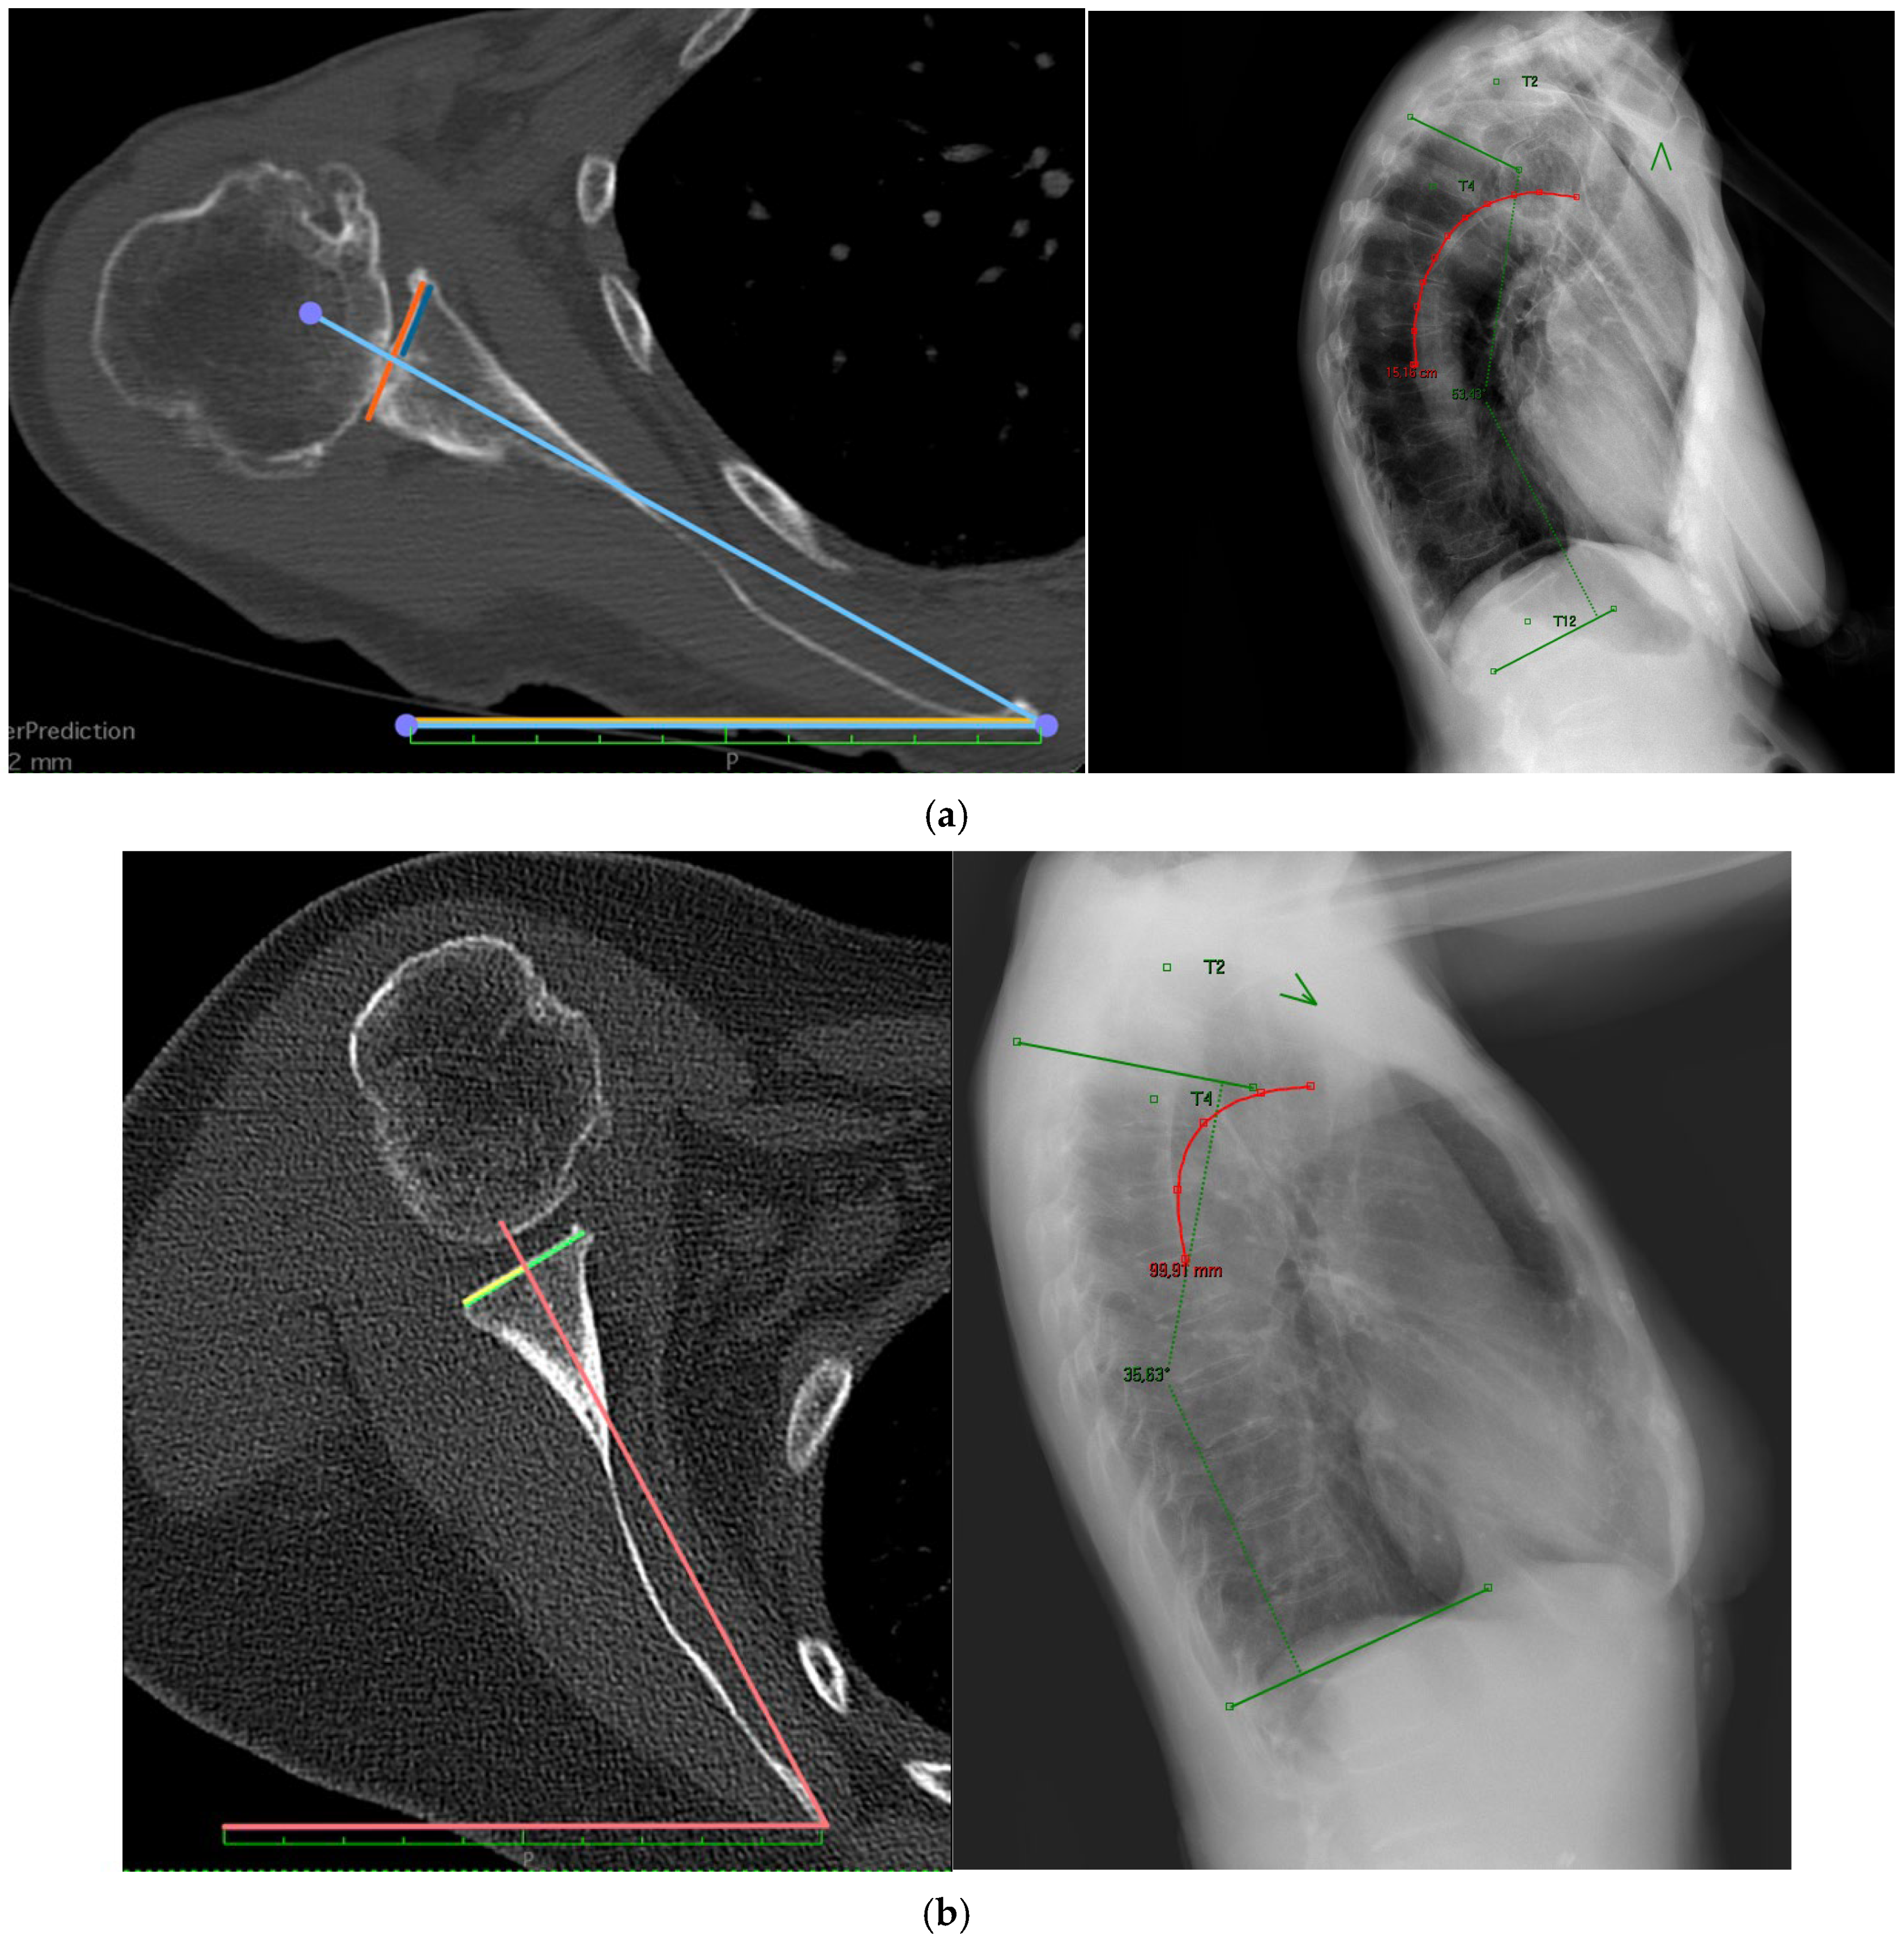

2.1. Radiological Analysis

| Cobb Angle | Scapular Internal Rotation | Anterior Scapular Tilt |

|---|---|---|

| 40.7 (12.4) | 41.9 (8.4) | 24.1 (13.3) |

| Cobb Angle | Scapular Internal Rotation (Mean (SD)) | p-Value | Anterior Scapular Tilt (Mean (SD)) | p-Value |

|---|---|---|---|---|

| ≤36 | 40.3 (9.3) | 0.047 | 25.8 (13.0) | 0.570 |

| >36–46 | 41.8 (7.8) | 23.3 (12.5) | ||

| ≥47 | 43.7 (8.0) | 23.5 (14.8) |